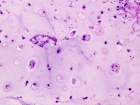

J.S. - 12 year old boy c/o right knee pain and swelling for ten days. Painful at rest, worse at night and with activity. Able to ambulate with pain. Initially the pain was accompanied by fever, chills, malaise, nausea and vomiting; all of which have resolved.

Zoom image: Cell stain Cell stain.